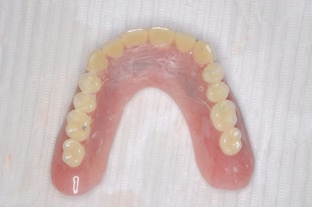

この方は結局、all on 4 を応用し、奥歯に両側2本のインプラントを傾斜埋入して、それにマグネットをつけました。これなら骨移植をせずにインプラントが可能になり、3ヶ月ほどで終了できます。

マグネットをつけているので大幅に義歯の面積を縮小することが可能になりました。

患者様も違和感がないと大喜びです。